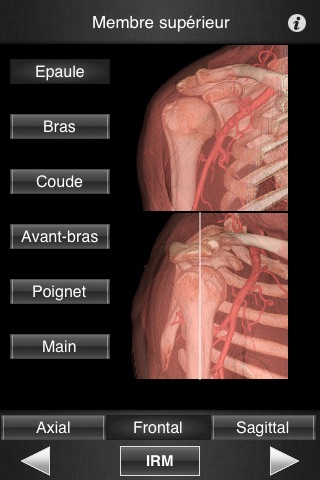

Il contient 502 coupes d’IRM jointives (2-4 mm dépaisseur) dans les trois plans de l’espace.

- Défilement fluide des images dans les trois plans de l’espace.

- Repérage précis du niveau de coupe grâce aux images 3D (Volume Rendering)